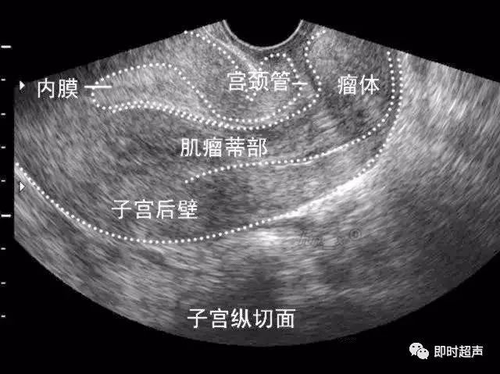

子宫肌层钙化灶是一种非常常见的子宫疾病。多数子宫肌层钙化灶是口服药物流产没能流干净或者是血块机化引起的。多数是不需要给予治疗,往往不会引起任何症状,而且钙化灶也相对比较小,建议在日常生活中定期的给予复查就可以。

还可能是遗传性的子宫钙化灶,有结核病病史的患者也可能导致子宫内膜钙化和异物,这种相对来说会比较严重一些,子宫内膜钙化只能通过宫腔镜检查或刮宫后的病理检查来确认。所以最好要先确定是哪种子宫钙化灶,这样才能判断出是否需要治疗。